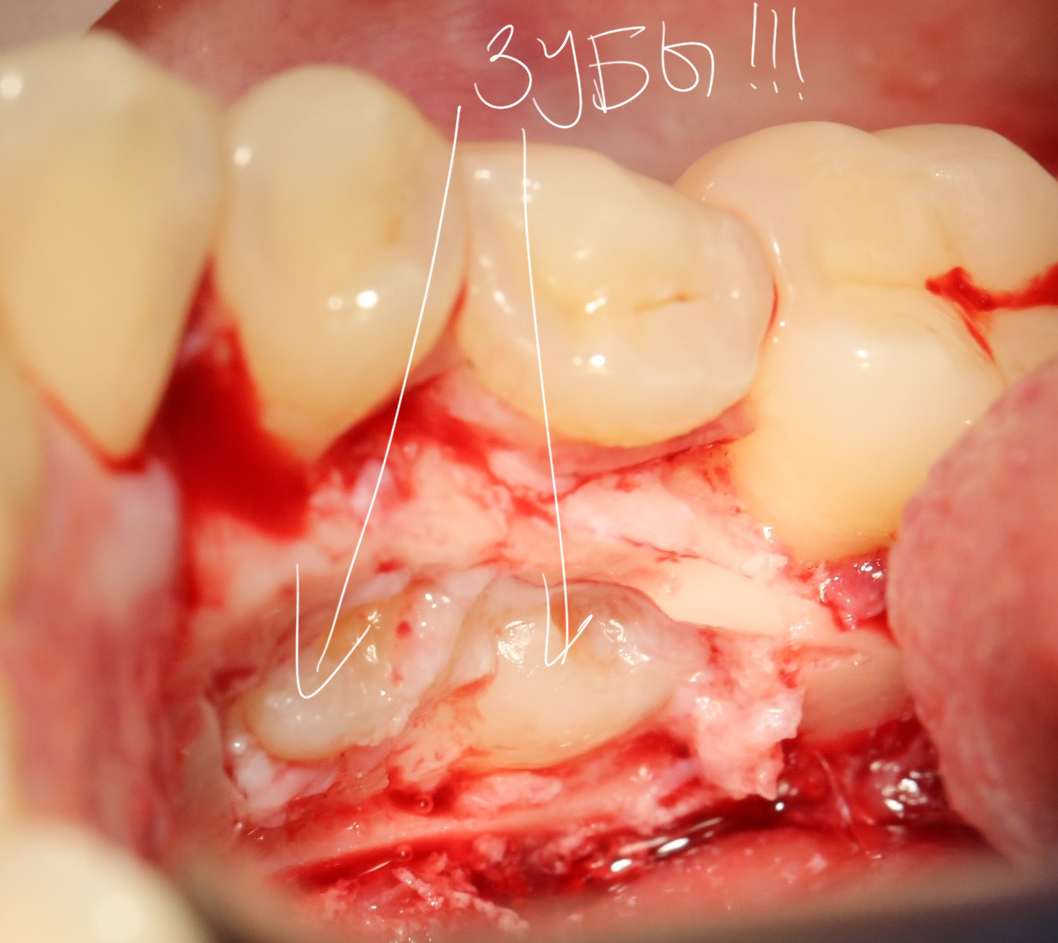

Костная «дверца» на время отделяется и убирается в физраствор, а мы видим следующее:

Это фолликулы и, частично, коронковые части сверхкомплектных зубов.

Теперь аккуратно нам нужно выделить сами зубы:

А вот они! Далее мы руководствуемся главным правилом хирурга-стоматолога: